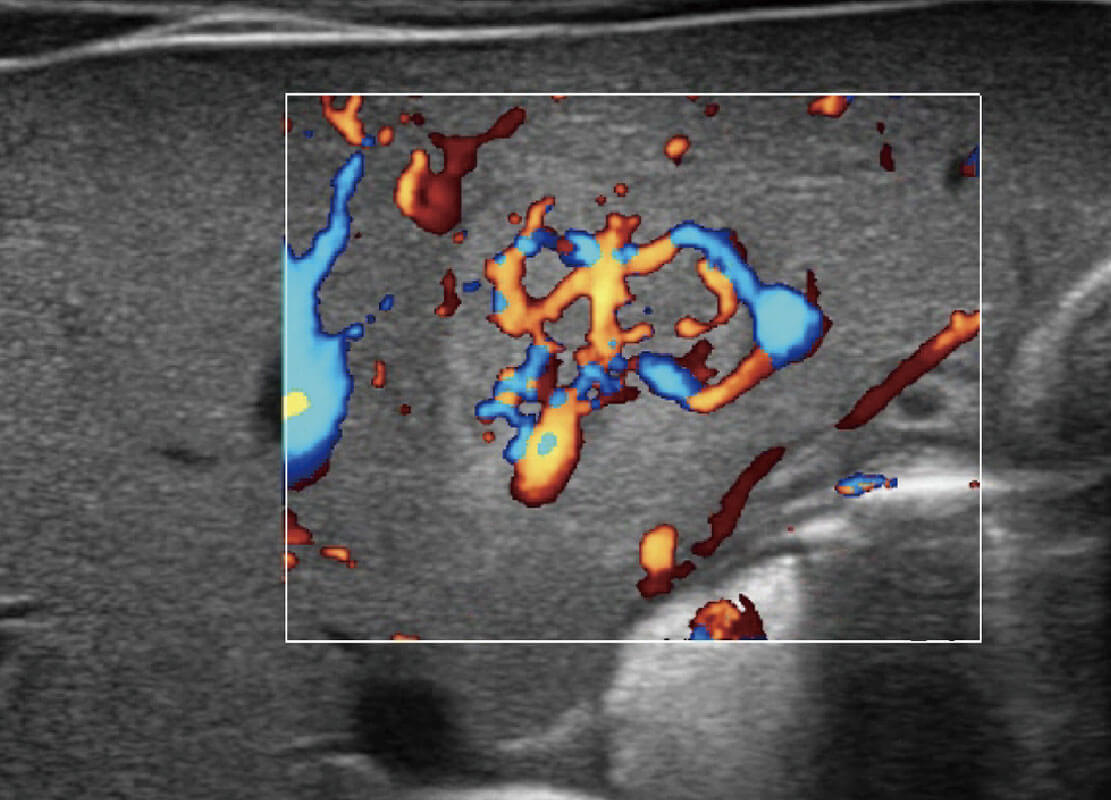

乳腺超声 / 新生儿

P60搭载宽频带线阵探头、宽景成像、弹性成像技术,为您提供乳腺全面应用方案。P60支持高频相控阵探头、线阵探头、腹部高频探头、腹部微凸探头等,丰富的探头群搭载敏感的彩色血流成像,适用于新生儿多种脏器检测要求,满足新生儿筛查需求。

• 乳腺癌显微血流